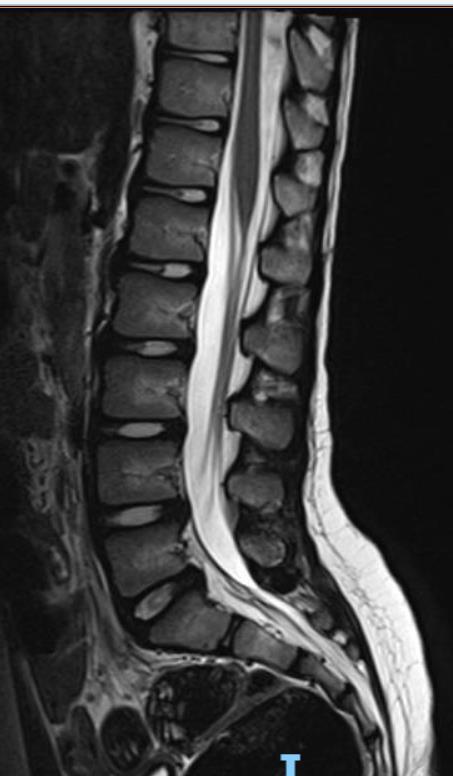

SDR involves surgically accessing the spinal cord (typically in the lumbosacral region, L2 to S1 or S2).The dorsal (sensory) nerve roots are carefully identified and then divided into smaller bundles called rootlets.

T10–12 spastic diplegia

C5–T2 spastic quadriplegia

C1–C4 secondary generalized dystonia